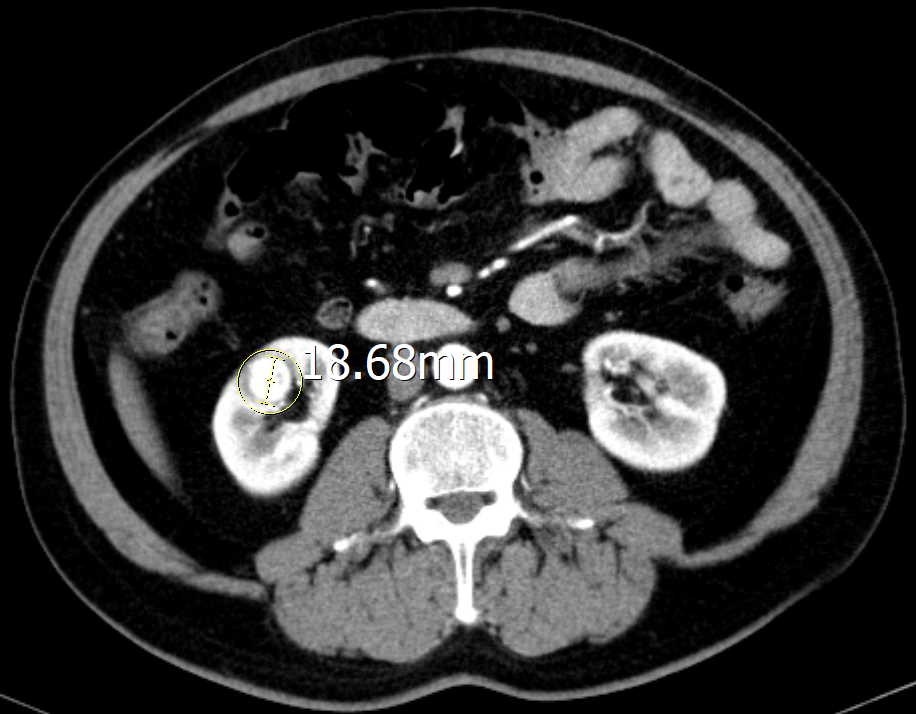

“结合相关影像资料,我们发现患者右肾皮质内见类圆形强化灶,直径约18mm,边界模糊不清,考虑恶性肿瘤。建议开展手术。”泌尿外科主任李胜文表示。

由于胡大爷的肾肿瘤隐匿于肾实质深处,被正常肾脏组织包裹,手术中肉眼无法观测,定位非常困难,肿瘤位置判断不准确,可能导致⼿术不彻底或损伤周围健康组织,因此必须借助其他⼿段辅助定位。